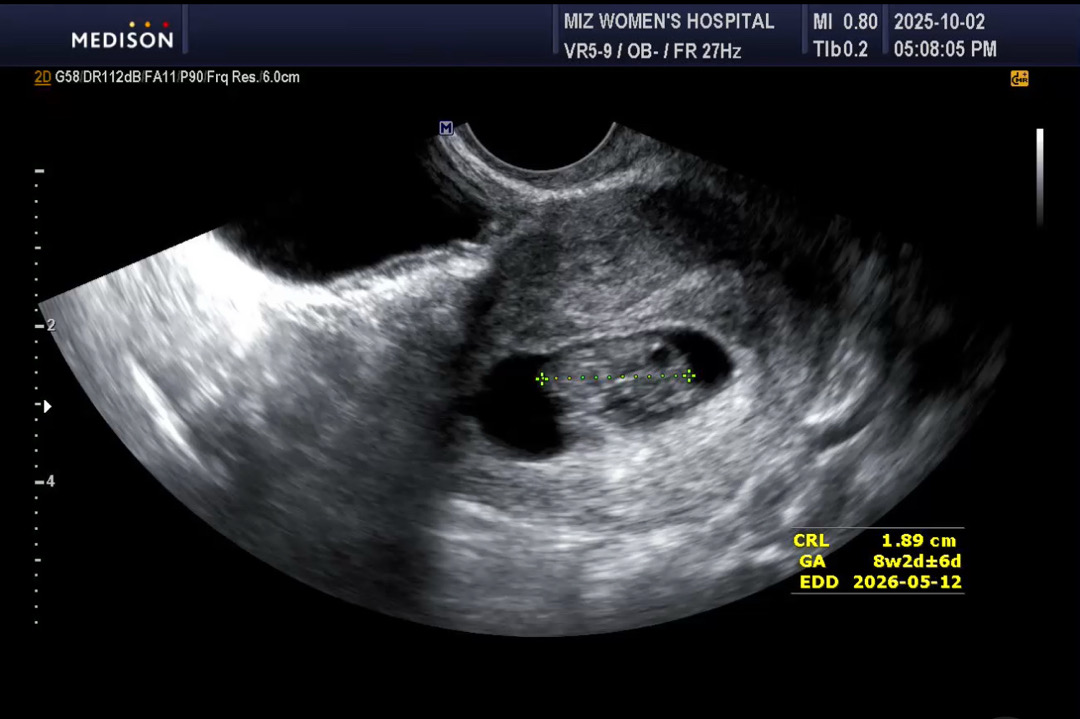

오늘 초음파 보고 왔는데 아기집이 작대요ㅠ

아이 크기는 주수랑 비슷하게 가고 있고 심장박동도 160정도로 아주 우렁찹니다..! 오늘 원장님께서 초음파 보시고는 자궁이 평균보다 좀 작은 편이고, 아기집도 많이 작다하셔서 조금 불안해요 ㅠㅠ 아기집 같은경우 갑자기 쑥 커지는 경우도 있다고 하시던데 저는 초반부터 현재 8주까지 계속 작다는 소리 들었어요... 혹시 저와 비슷한 분 계실까요...?🥺